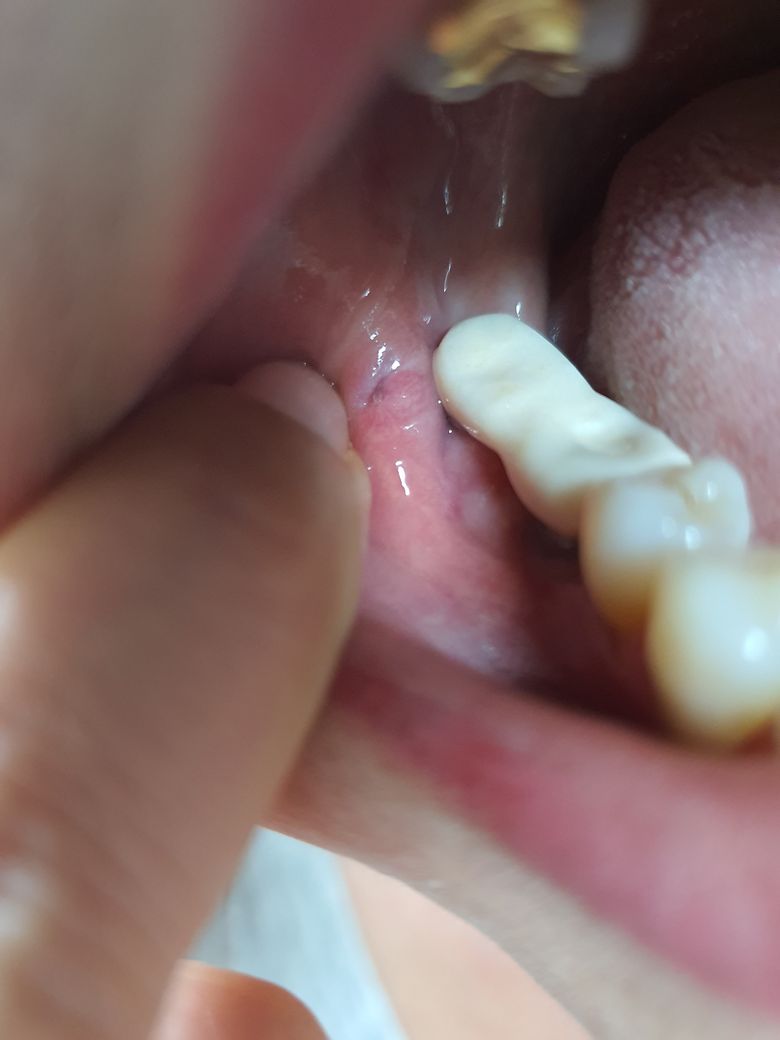

치과치료 도중 볼살이 찢어졌어요 괜찮을까요?

임플란트 기둥을 깎다가 볼 살을 기계로 왔다갔다 찢으셨어요 치과원장님이..

꽤 깊은데 아물어 가긴 하는데 오늘은 갑자기 좀 매운거 먹었더니 시렵더라구요

• 1번 째 사진